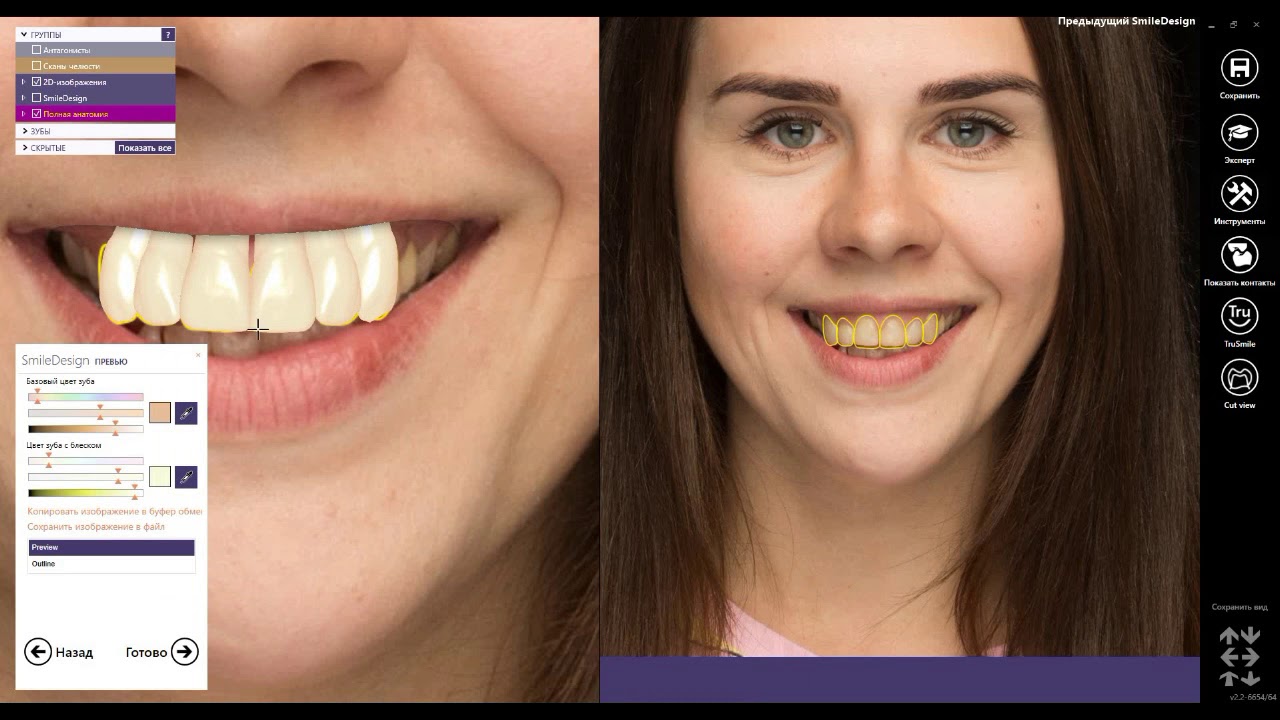

3shape Smile Design

Immerse yourself in the artistic beauty of 3shape Smile Design through substantial collections of inspiring images. blending traditional techniques with contemporary artistic interpretation. transforming ordinary subjects into extraordinary visual experiences. The 3shape Smile Design collection maintains consistent quality standards across all images. Ideal for artistic projects, creative designs, digital art, and innovative visual expressions All 3shape Smile Design images are available in high resolution with professional-grade quality, optimized for both digital and print applications, and include comprehensive metadata for easy organization and usage. Our 3shape Smile Design collection inspires creativity through unique compositions and artistic perspectives. Instant download capabilities enable immediate access to chosen 3shape Smile Design images. Our 3shape Smile Design database continuously expands with fresh, relevant content from skilled photographers. The 3shape Smile Design collection represents years of careful curation and professional standards. Diverse style options within the 3shape Smile Design collection suit various aesthetic preferences. Multiple resolution options ensure optimal performance across different platforms and applications. Professional licensing options accommodate both commercial and educational usage requirements. Each image in our 3shape Smile Design gallery undergoes rigorous quality assessment before inclusion. Time-saving browsing features help users locate ideal 3shape Smile Design images quickly. Advanced search capabilities make finding the perfect 3shape Smile Design image effortless and efficient.